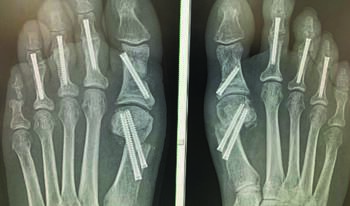

As demonstrated, postoperative protocol for many procedures depends on surgeon preference. Minimally invasive bunion surgery is no exception. Further discussion surrounding postoperative protocol is necessary for optimal patient outcomes. In our experience, one must consider several factors including the incision, osteotomy stability and fixation selection. Due to the minimal incisions, only a few sutures are necessary for closure, making incisional concerns a small component of postoperative decision-making. With less soft tissue disruption, we find patients often have substantially less pain and opioid use.

One concern to those new to minimally invasive bunion surgery is that for stability of the transverse osteotomy technique as employed and described by Siddiqui and colleagues.10 A recent publication by Aiyer and coworkers looked at biomechanical stability of the minimally invasive approach via a chevron or transverse osteotomy.11 In this cadaveric study, the authors found no statistically significant difference between methods of osteotomy for failure after cyclic loading. Though not statistically significant, the transverse osteotomy performed slightly better when it came to failure when compared with the chevron method of correction.11 In addition to this report, Siddiqui and team had no nonunions and excellent radiographic outcomes in their on 218 feet that underwent minimally invasive transverse osteotomy for bunion correction at four weeks.12

The initial technique employed with no internal fixation and use of a 2.0 mm Steinman pin saw more callus formation from secondary bone healing, but still allowed for immediate postop weight bearing.12 However, there was a higher risk noted for pin site infection.13 Internal fixation provides direct fixation of the capital fragment, yielding less callus formation, but enhanced direct stability. Additionally, with inherent minimal dissection associated with a minimally invasive approach, the soft tissue structures surrounding the osteotomy provide enhanced stability.13 The capital fragment maintains the tibial and fibular sesamoid ligament attachments along with the dorsal and plantar capsule/soft tissue attachments normally disrupted in open surgery.13 The literature and the authors experience support that it is safe for patients to ambulate immediately postop in these minimally invasive cases.

The authors’ standard postoperative protocol for minimally invasive bunion surgery cases include immediate weight bearing in a postoperative shoe. Patients’ postoperative dressings, which consist of 4x4 gauze, ABD pads, cast padding and an Ace bandage stay intact until their first postoperative follow-up appointment in one to two weeks. After this dressing removal, patients can begin showering with regular soap and water. We instruct them to place a silicone gel toe spacer in the first interdigital space at the time of their first visit and to begin gentle range of motion exercises of the first metatarsophalangeal joint. Siddiqui and colleagues describe, that unlike with open surgery with capsular dissection, this extracapsular dissection supports early first metatarsophalangeal joint range of motion, further preventing capsular scarring or adhesions.12 This also contributes to why patients rarely report first metatarsophalangeal joint stiffness postoperatively with these minimally invasive techniques.14

It is imperative to note that one must evaluate postoperative radiographs for alignment and osseous bridging, however one will not be able to visualize full radiographic union at the time one releases the patient to full activity. The clinical exam is still the most important piece of the postoperative course progression, in our experience. We advise patients to keep their silicone gel insert in the first interdigital space until 12 weeks postop, as the soft tissue structures realign to the corrected anatomic location. We obtain postoperative radiographs at two weeks, four weeks, eight weeks, and 12 weeks postoperatively.